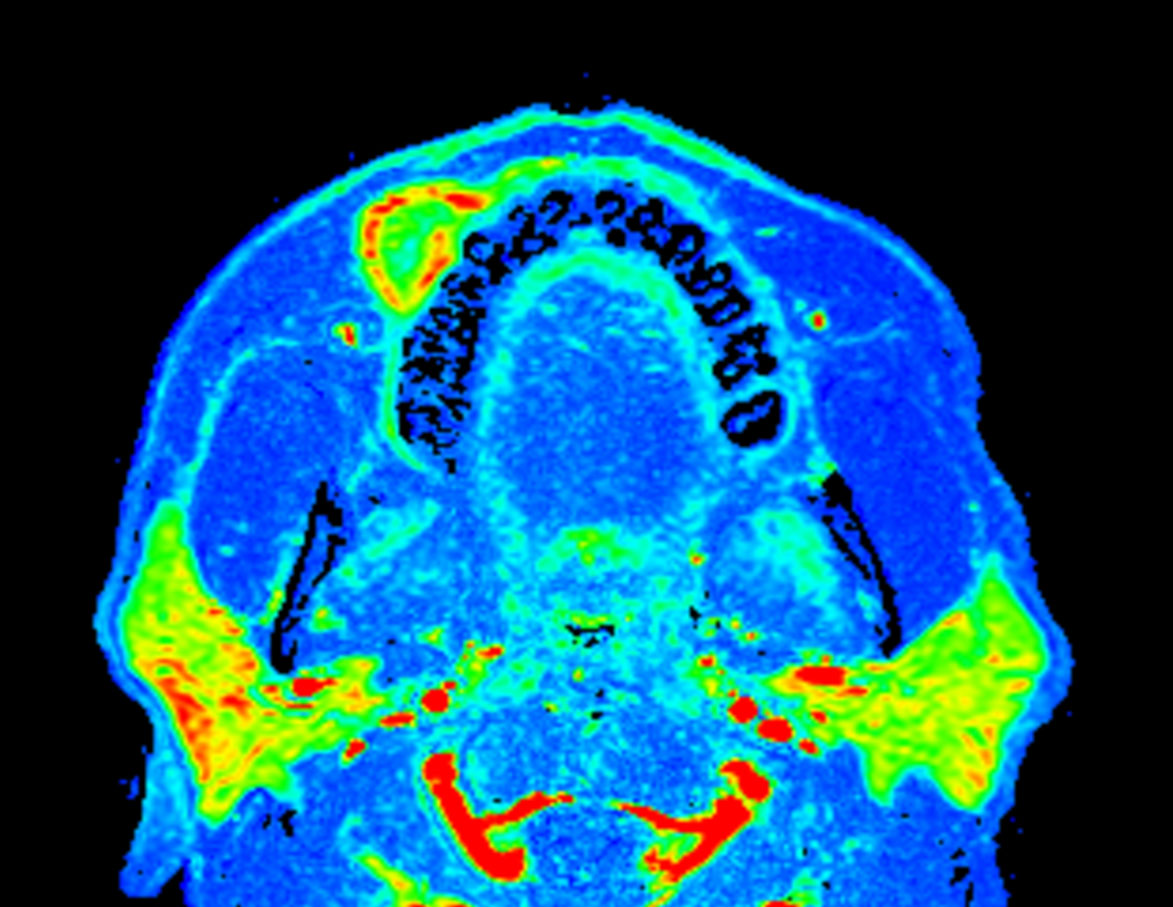

Axial eTHRIVE (area under the curve)

Axial eTHRIVE (max enhancement)

Axial eTHRIVE (wash-in)